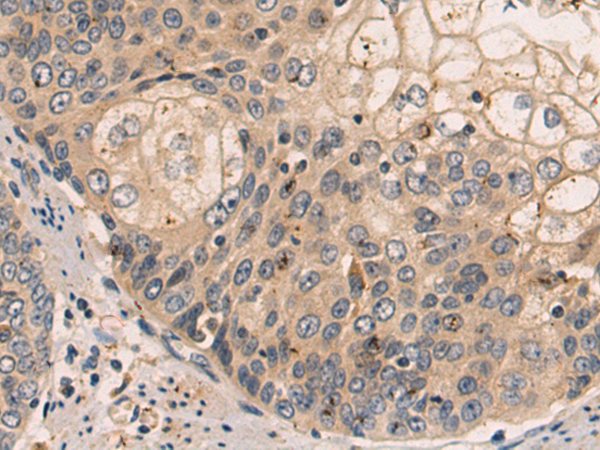

分类: 科研抗体货号: P08334别名: KYOT; SLIM; FHL-1; FHL1A; FHL1B; FLH1A; SLIM1; XMPMA; SLIM-1; SLIMMER应用: WB,IHC反应种属: Human, Mouse, Rat